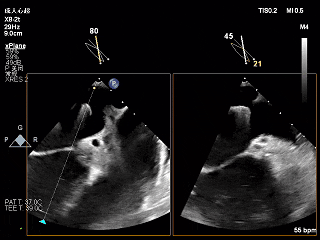

3D下大鞘的穿刺位置大概在3点钟方向

左房较大,完成骑跨

“+M”使夹子垂直于瓣环平面

“弹”道测试

打开夹子,调整轴向

3D上彩确认夹子位置

2维上彩确认夹子位置

夹子关小进入左心室

瓣下打开夹子确认轴向